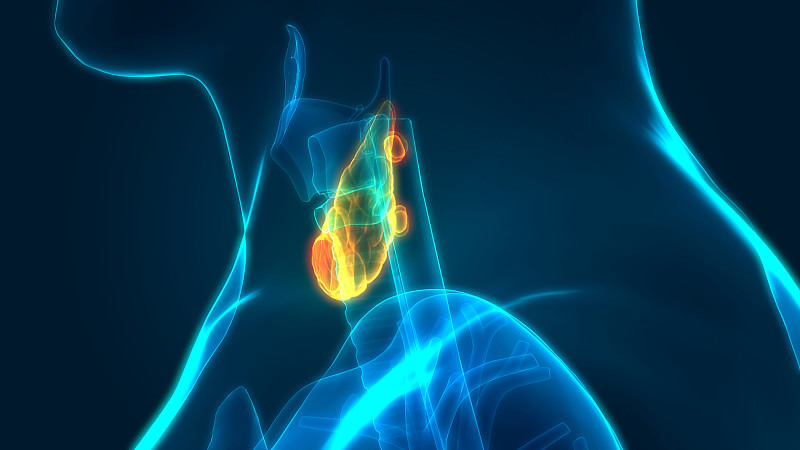

人体腺体甲状腺解剖学详情

人体腺体甲状腺解剖学详情

人体腺体甲状腺解剖学详情

人体腺体甲状腺解剖学详情

人体腺体甲状腺解剖学详情

人体腺体甲状腺解剖学详情

人体腺体甲状腺解剖学详情

人体腺体甲状腺解剖学详情

人体腺体甲状腺解剖学详情

人体腺体甲状腺解剖学详情

人体腺体甲状腺解剖学详情